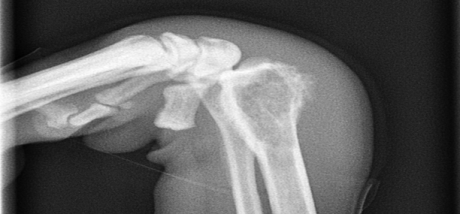

Ακτινολογικη διερευνυση περιστατικου με πανοστειτιδα σε νεαρο σκυλο german shepherd 11 μηνων,με ταυτοχρονη ρηξη προσθιου χιαστου συνδεσμου.